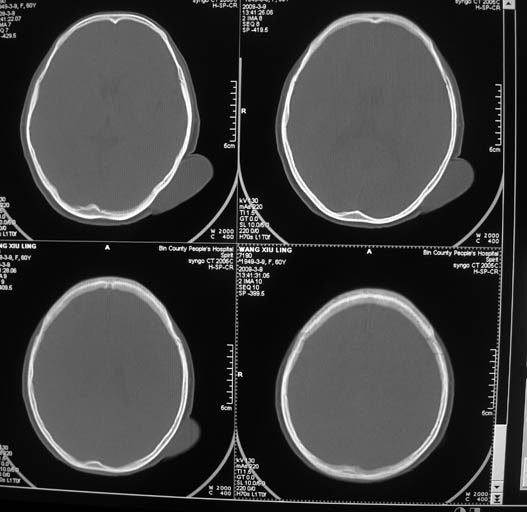

标题: CT18574:女,60岁,头部肿物。

女,60岁,头部肿物。ct值为12hu。

左枕区头皮纤维瘤可能性大。

考虑-----皮脂腺瘤或皮样囊肿可能性大

左枕部软组织影,考虑皮样囊肿?最好穿刺!

至此考虑皮样囊肿